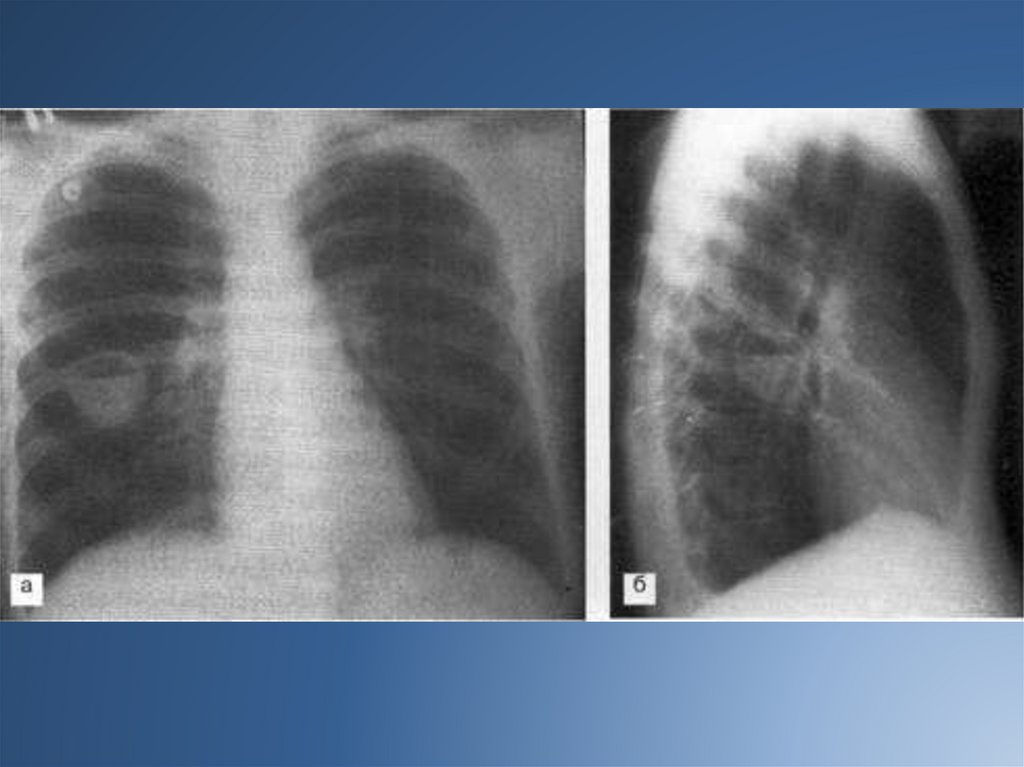

На рентгенограмме рисунок легких носит сотовый или ячеистый характер, иногда

выявляются полостные образования, вокруг которых могут быть воспалительные

инфильтраты.

При стихании процесса проводят контрастную бронхографию для выявления характера и

локализации бронхоэктазов с целью последующего возможного оперативного их

удаления.